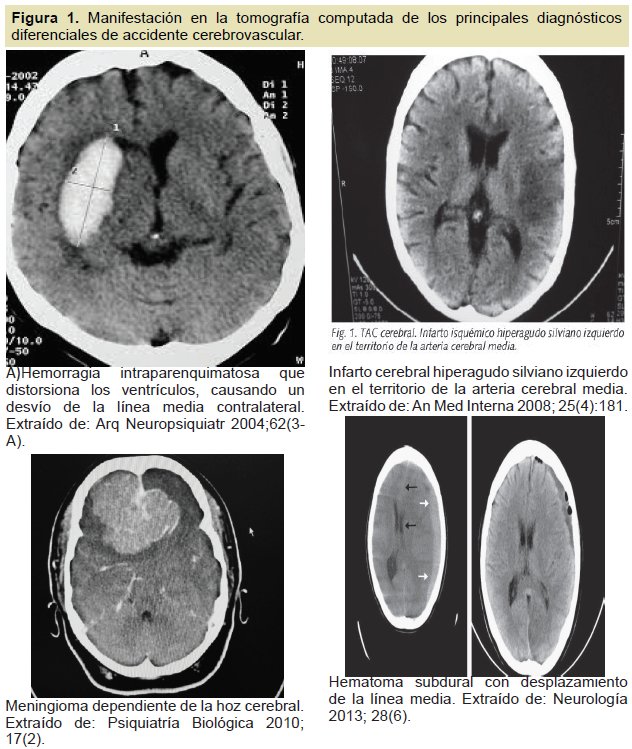

Imitadores Del Ictus Un Reto Para El Medico De Urgencias